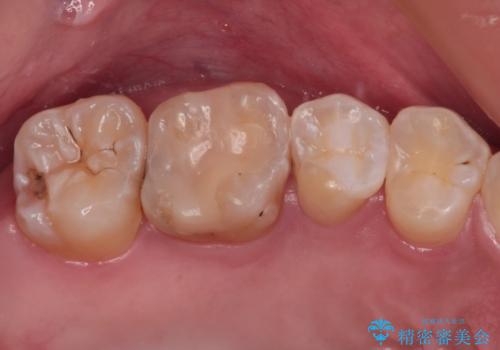

- 以前詰め物をした奥歯に物が頻繁に挟まるとのことで来院された患者様です。

充填物は形態が不正であり、歯肉付近にバリのように充填材料が飛び出していたため、歯肉が腫れやすい状態でした。

精密に治療を行うため、型取りを行った上でセラミックインレーによる修復治療を行うこととしました。